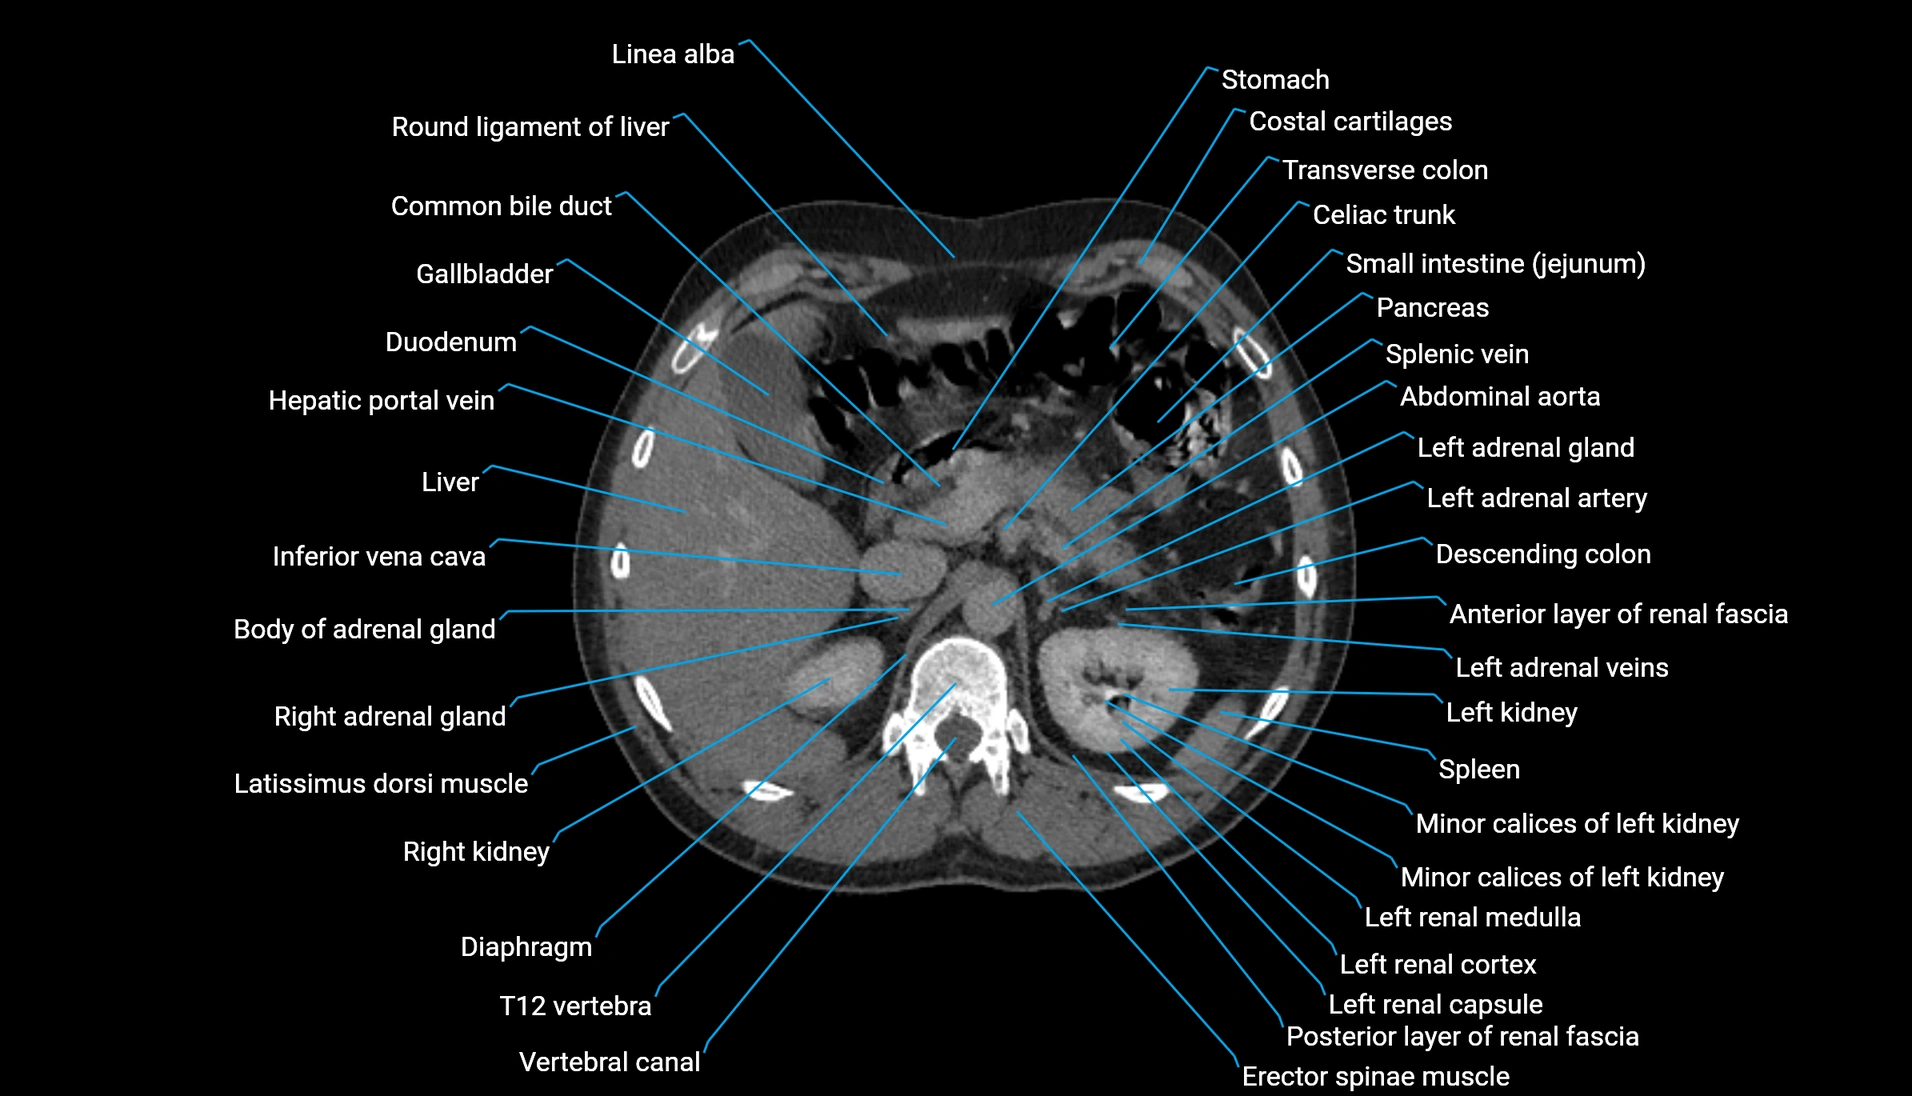

CT Appearance

Non-contrast CT:

-

Demonstrates cortical bone of acetabular rim in excellent detail

Detects fractures, dysplasia, retroversion, or bony overcoverage (pincer impingement)

3D reconstructions used in preoperative hip surgery planning

CT VRT 3D image

CT image